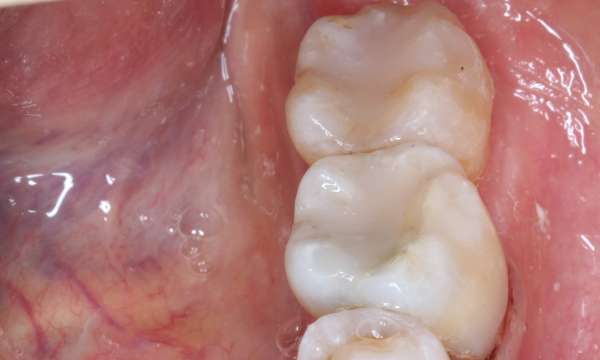

Safe Mercury Removal Technique

Biological Dentistry

Before

After